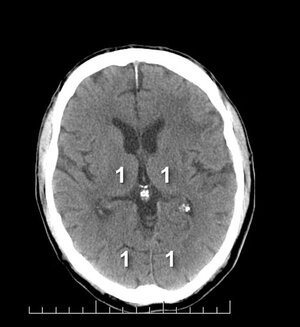

pc-ASPECTS — Niveau thalamique : T (thalamus), OL (lobe occipital)

Niveau thalamique

T Thalamus · OL Lobe occipital